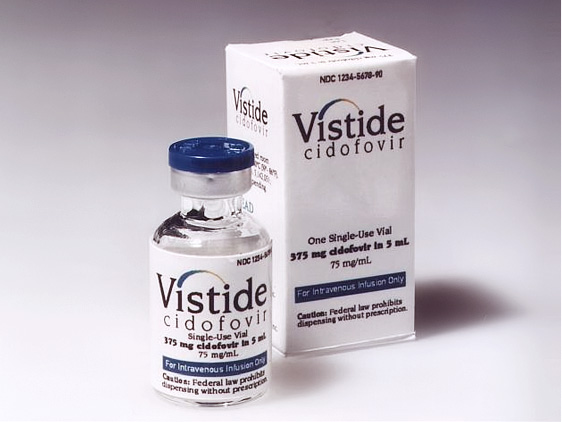

후두미세수술과 함께 항바이러스제인 vistide(cidofovir)을 환부에 주입하는 방법을 사용하고 여러번의 수술로 반흔조직이 많거나 종양이 넓게